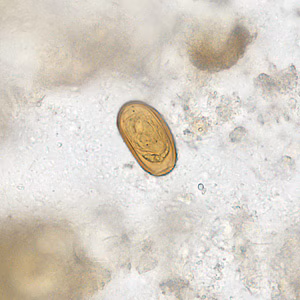

Case #281 – August, 2010

A twenty-year-old male from India presented with recurrent abdominal pain. He underwent an appendectomy at a local medical center. Sections of the appendix were obtained, sectioned, and stained with hematoxylin and eosin (H&E). Figures A–D show what was observed microscopically. What is your diagnosis? Based on what criteria?

Figure C